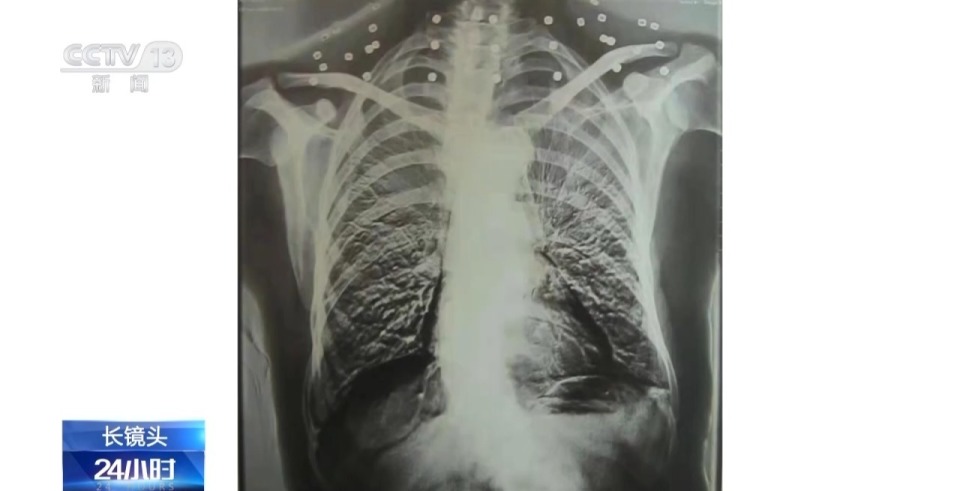

吴以先:21、22、23、24、25、26、27、28、29、30、33个,还有其他地方有,这里还有一个弹片。

记者:腹部还有弹片。

吴以先:腹部有弹片,加起来是33个。

吴以先:体检医生发现的,他一看,他说像一串项链一样的,他说你看这个病人脖子上的项链都没有取下来,好大一串项链。我说我从来没有戴过项链,这不是项链吧,我说是不是弹片,你们看看。

直到现在,吴以先体内的弹片也还没有取出,每到天气变化的时候,留有弹片的部位都会有痛感。

吴以先:平时要注意活动,按按手,按按腹部,胸部到处都有弹片,这样按摩之后疼痛缓和一点,不怎么疼了,心情上也很舒畅。